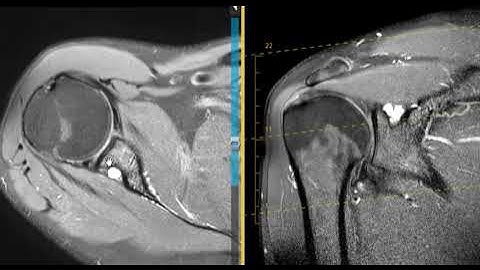

Suprascapular nerve compression from large paralabral cyst